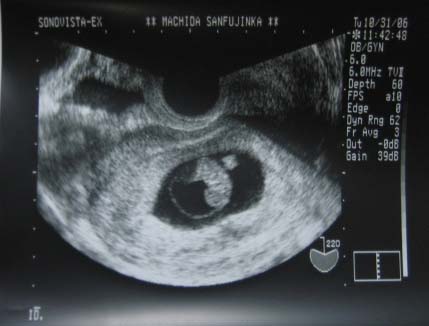

そのときの写真がコレ↓

前回の診察から10日で結構成長しててびっくり。下の丸っこいのが頭らしいです。前回はただのマル?だったのに

結果は「赤ちゃんは無事ですね。でも1週間自宅で安静にしていてください」とのこと。そして1週間後に再度診察です。やっぱりちょっと出血していて、これがひどくなってばい菌が子宮に到達してしまうと流産になってしまうそうです。